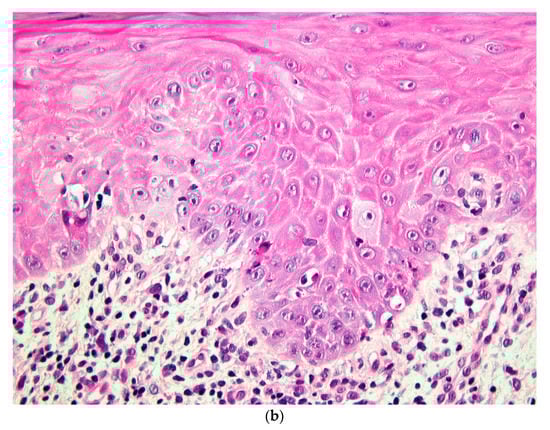

A biopsy of the right buccal mucosa was performed. Histopathological examination revealed a stratified squamous epithelium with focal atrophy and discreet parakeratosis. The superficial chorion contained a band-like dense inflammatory infiltrate, composed mostly of lymphocytes and macrophages, with very rare eosinophils. Apoptotic keratinocytes in the basal layer were observed (Figure 2a,b). These features were consistent with an active lichen planus or a drug-induced lichenoid reaction.

Figure 2.

(a) Histopathological section showing parakeratotic partly atrophic squamous epithelium with a band-like dense inflammatory infiltrate in the superficial chorion (HE stain, ×10). (b) Higher magnification showing inflammatory lymphocytic infiltrate and apoptotic bodies in the basal layer (HE stain, ×40).